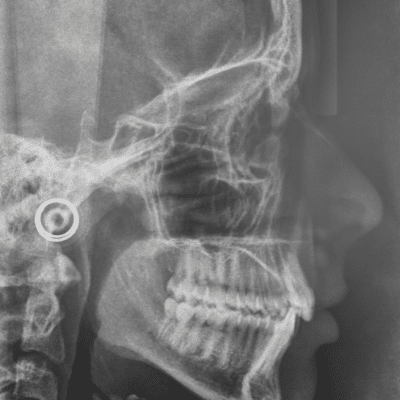

One of the most significant changes in orthodontic treatment is in the imaging process. When you visit our office for the first time, you will have a consultation that includes taking images of your teeth and mouth structure. In the past, a series of x-rays had to be taken to help the orthodontist get a clear view of your mouth so that she could determine your specific orthodontic needs. However, today’s imaging is much quicker and less invasive. Advanced orthodontic imaging includes intraoral scanning technology that allows the orthodontic assistant to capture precise images of your teeth in approximately 5 minutes. The best part is, with a nice scan, there’s no need to have messy impressions taken.